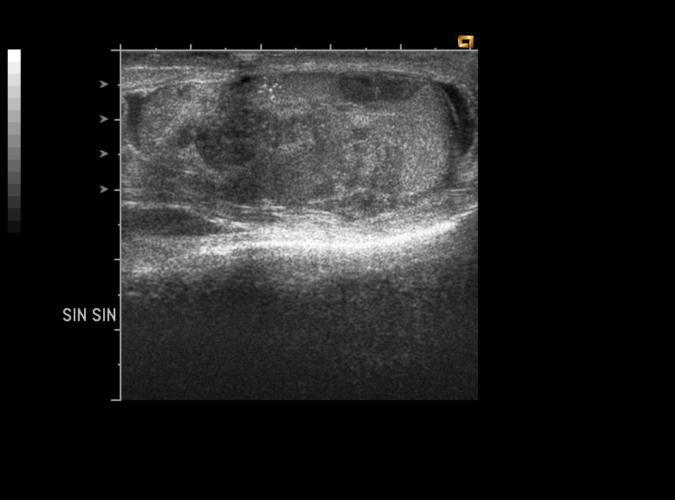

av Catherine Olsson, sonograf

Patologi.

Long. 45årig med vänstersidig testistumör.